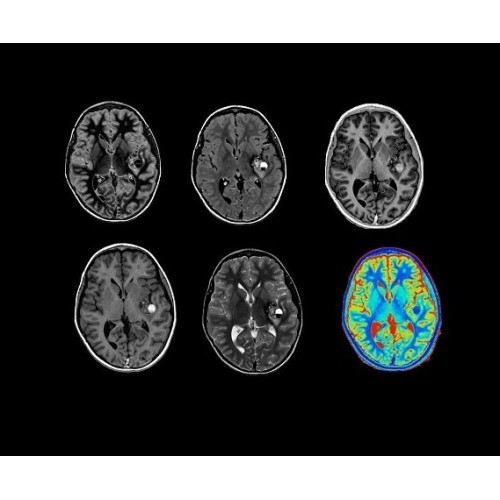

SIGNA Architect 3.0T — это новейший МРТ аппарат компании GE, который предлагает высочайший уровень производительности — в системе 128 приемных каналов, 48 канальная катушка головы, полный спектр клинических возможностей. Высокий уровень комфорта пациента обеспечивают такие особенности как отсоединяемый стол, положение пациента «ногами вперед» для всех видов исследований, SilentWorks — бесшумное и MAGIC — быстрое сканирование.

Теперь возможности МРТ поражают еще больше благодаря ультрасовременным решениям для визуализации с SIGNA Architect 3.0 Тл, объединяющей новейшие достижения в области МР-технологий и интуитивно понятный интерфейс. Система SIGNA Architect, разработанная на базе новой платформы SIGNA Works, представляет собой гармоничное сочетание дизайна и функциональности. Каждый элемент системы направлен на повышение производительности, эффективности клинической практики, финансовых показателей, а также комфорта и безопасности пациента.

Поле обзора 50x50x50 см и апертура шириной 70 см позволят достоверно визуализировать сложные анатомические области для пациентов с крупным телосложением, например, плечи и бедра. Феноменальная однородность системы SIGNA Architect обеспечивает наиболее широкое поле обзора с улучшенными характеристиками градиентов. Ничто не останется незамеченным.

Стандартный пакет приложений SIGNA Works позволит вам достичь желаемых результатов в клинической практике благодаря набору высокоэффективных средств визуализации. Программные приложения, входящие в состав данных клинических пакетов, включают широкий спектр контрастов, функции обработки 2D- и 3D-данных, а также возможность коррекции артефактов движения. SIGNA Works предоставляет набор инструментов, необходимых для проведения эффективного клинического исследования.

• NeuroWorks — универсальное решение для визуализации анатомии головного мозга, позвоночника, сосудов и периферических нервов с четкой дифференциацией тканей.